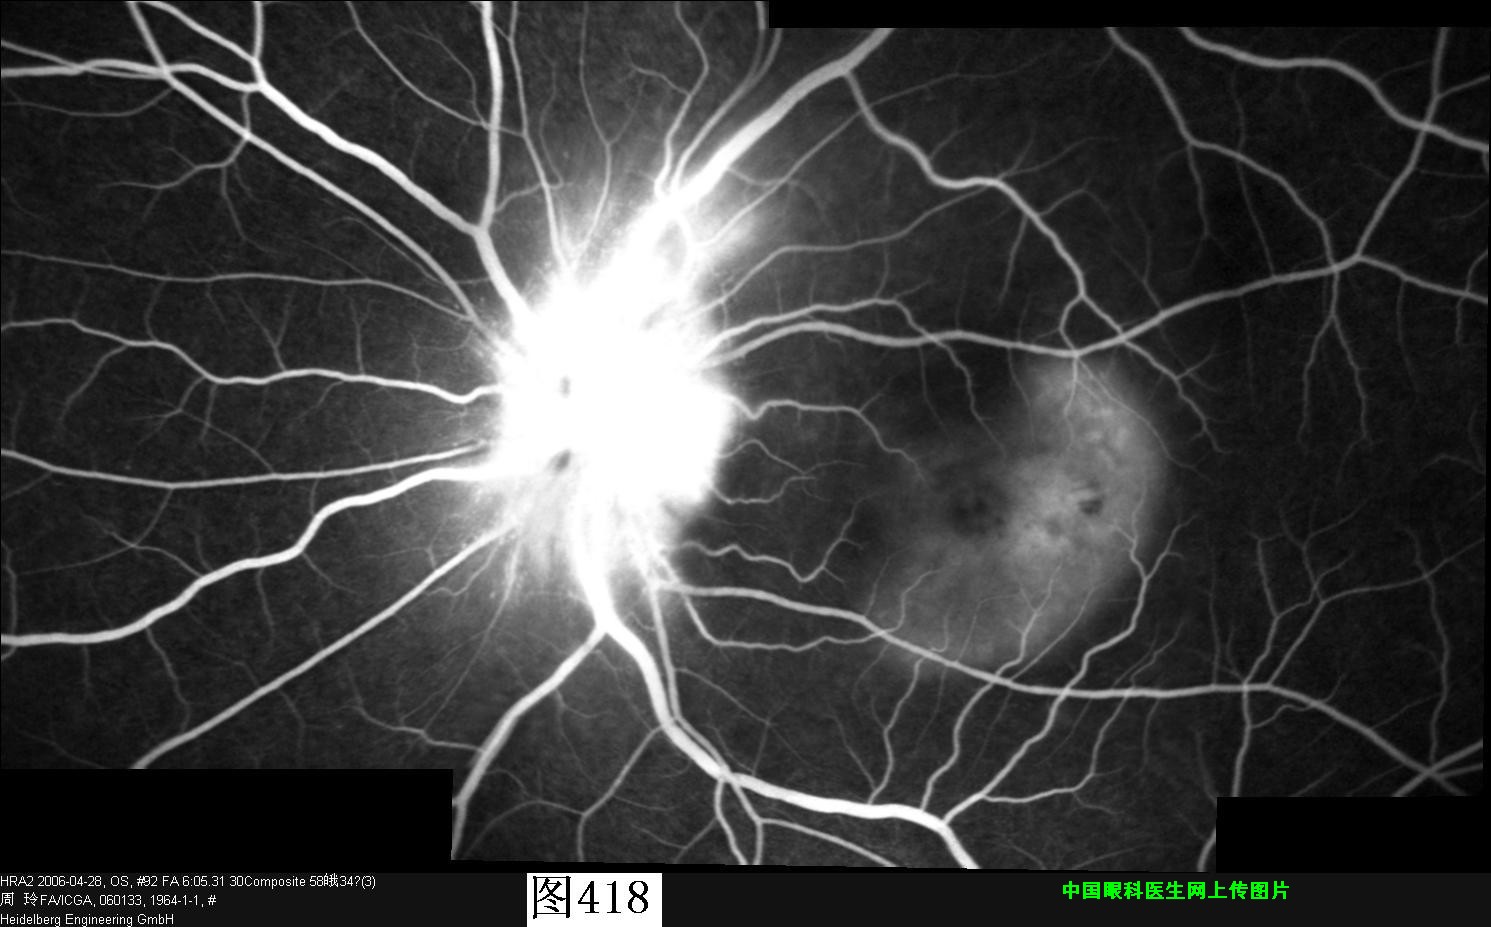

417 418 419 420